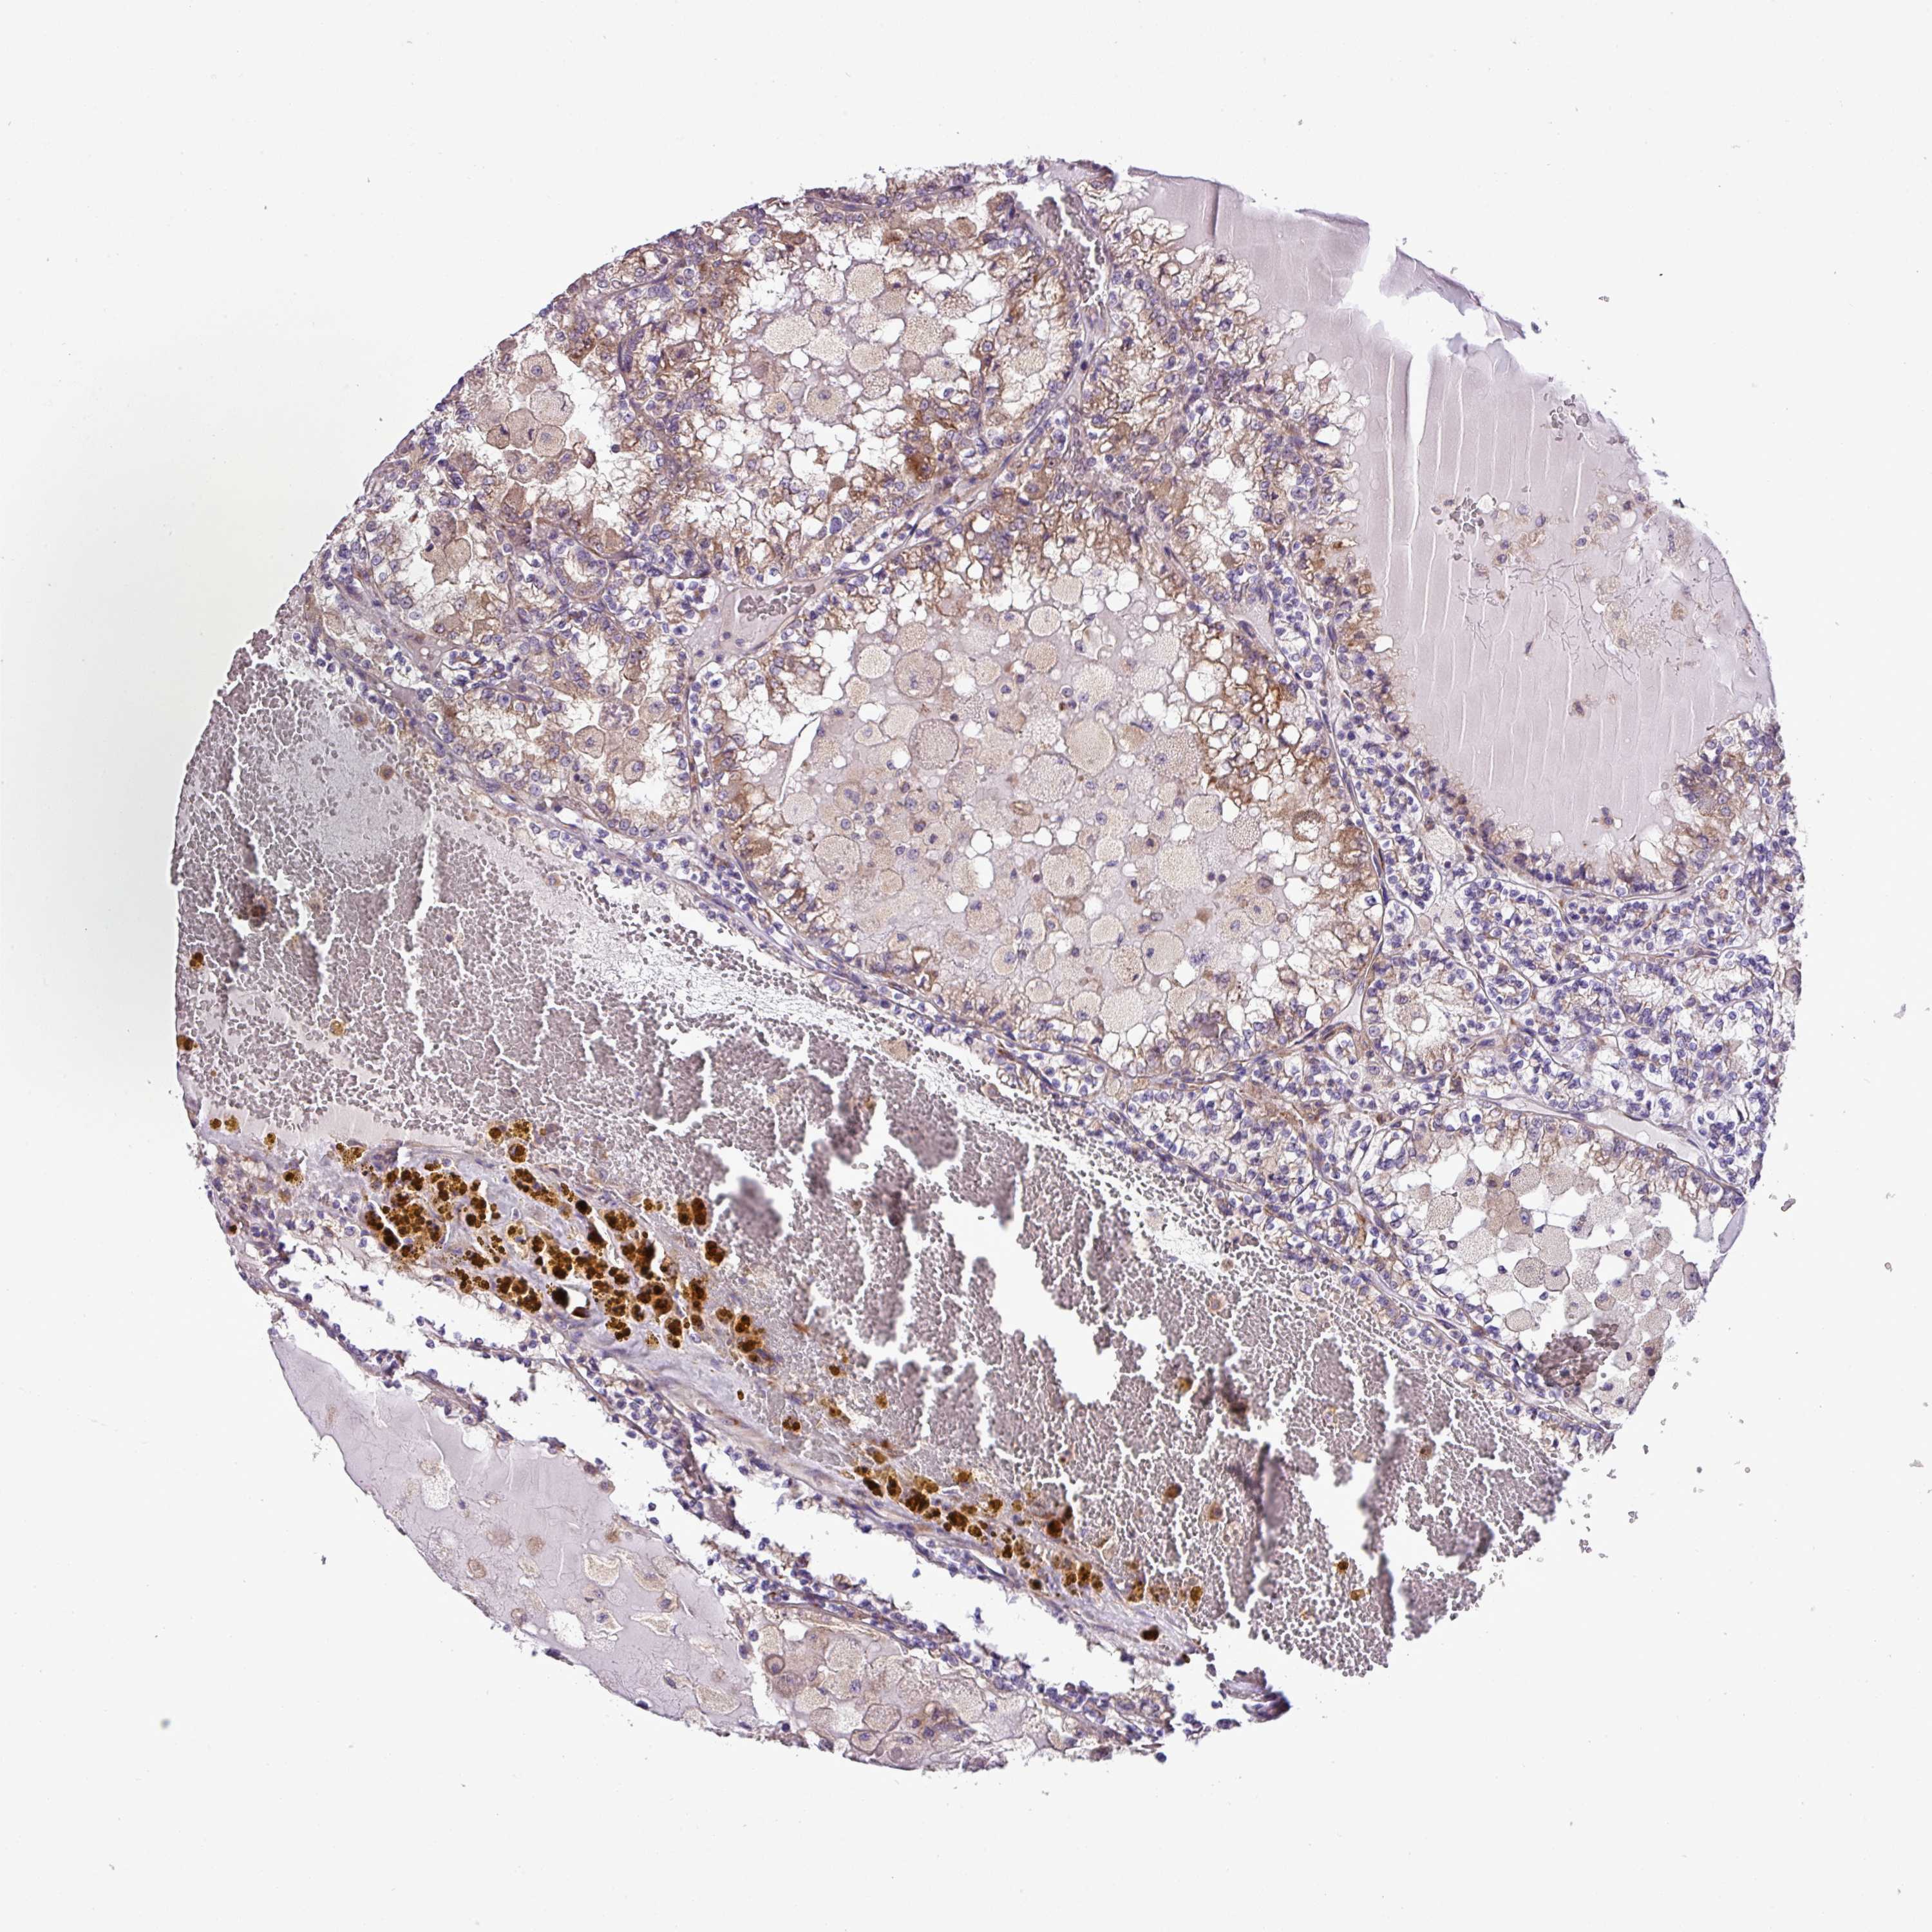

KIDNEY RENAL CLEAR CELL CARCINOMA (VALIDATION) - Interactive survival scatter ploti

The Survival Scatter plot shows the clinical status (i.e. dead or alive) for all individuals in the patient cohort, based on the same data that underlies the corresponding Kaplan-Meier plots. Patients that are alive at last time for follow-up are shown in blue and patients who have died during the study are shown in red.

The x-axis shows the expression levels (FPKM) of the investigated gene in the tumor tissue at the time of diagnosis. The y-axis shows the follow-up time after diagnosis (years). Both axes are complimented with kernel density curves demonstrating the data density over the axes. The top density plot shows the expression levels (FPKM) distribution among dead (red) and alive patients (blue). The right density plot shows the data density of the survived years of dead patients with high and low expression levels respectively, stratified using the cutoff indicated by the vertical dashed line through the Survival Scatter plot. This cutoff is automatically defined based on the FPKM cutoff that minimizes the p-score. The cutoff can be changed by dragging the vertical line or by entering a cutoff value in the square labeled "Current cut-off".

Under the Survival Scatter plot the p-score landscape (black curve; left axis) is shown together with dead median separation (red curve; right axis). Dead median separation is the difference in median mRNA expression between patients who have died with high and low expression, respectively. It is calculated as follows: median FPKM expression of dead patients with high expression - median FPKM expression of dead patients with low expression. This is intended to aid the user in visually exploring custom cutoffs and the associated p-scores and dead median separation.

Individual patient data is displayed and can be filtered by clicking on one or more of the category buttons on the top of the page. Categories describing expression level and patient information include: high, low, alive, dead, female, male and tumor stages. The scale of the x-axis can be toggled between linear and log-scale by clicking on the "x log" button. Mouse-over function shows TCGA ID, patient information and mRNA expression (FPKM) for each patient.

& Survival analysisi

Kaplan-Meier plots summarize results from analysis of correlation between mRNA expression level and patient survival. Patients were divided based on level of expression into one of the two groups "low" (under cut off) or "high" (over cut off). X-axis shows time for survival (years) and y-axis shows the probability of survival, where 1.0 corresponds to 100 percent.

RPL13 is not prognostic in Kidney Renal Clear Cell Carcinoma (validation)

Best expression cut offi

Based on the FPKM value of each gene, patients were classified into two groups and association between prognosis (survival) and gene expression (FPKM) was examined. The best expression cut-off refers the FPKM value that yields maximal difference with regard to survival between the two groups at the lowest log-rank P-value. Best expression cut-off was selected based on survival analysis .

When clicking on this number, the vertical dashed line indicating cut-off, the interactive survival plot, and the Kaplan-Meier curve will be adjusted to show results based on the best expression cut-off.

: 3176.24

P scorei

Log-rank P value for Kaplan-Meier plot showing results from analysis of correlation between mRNA expression level and patient survival.

N/A

TCGA RNA samplesi

RNA-seq data is reported as average FPKM (number Fragments Per Kilobase of exon per Million reads), generated by the The Cancer Genome Atlas (TCGA) .

Normal distribution across the dataset is visualized with box plots, shown as median and 25th and 75th percentiles. Points are displayed as outliers if they are above or below 1.5 times the interquartile range. FPKM values of the individual samples are presented next to the box plot.

Average pTPM 2564.9

Number of samples 100